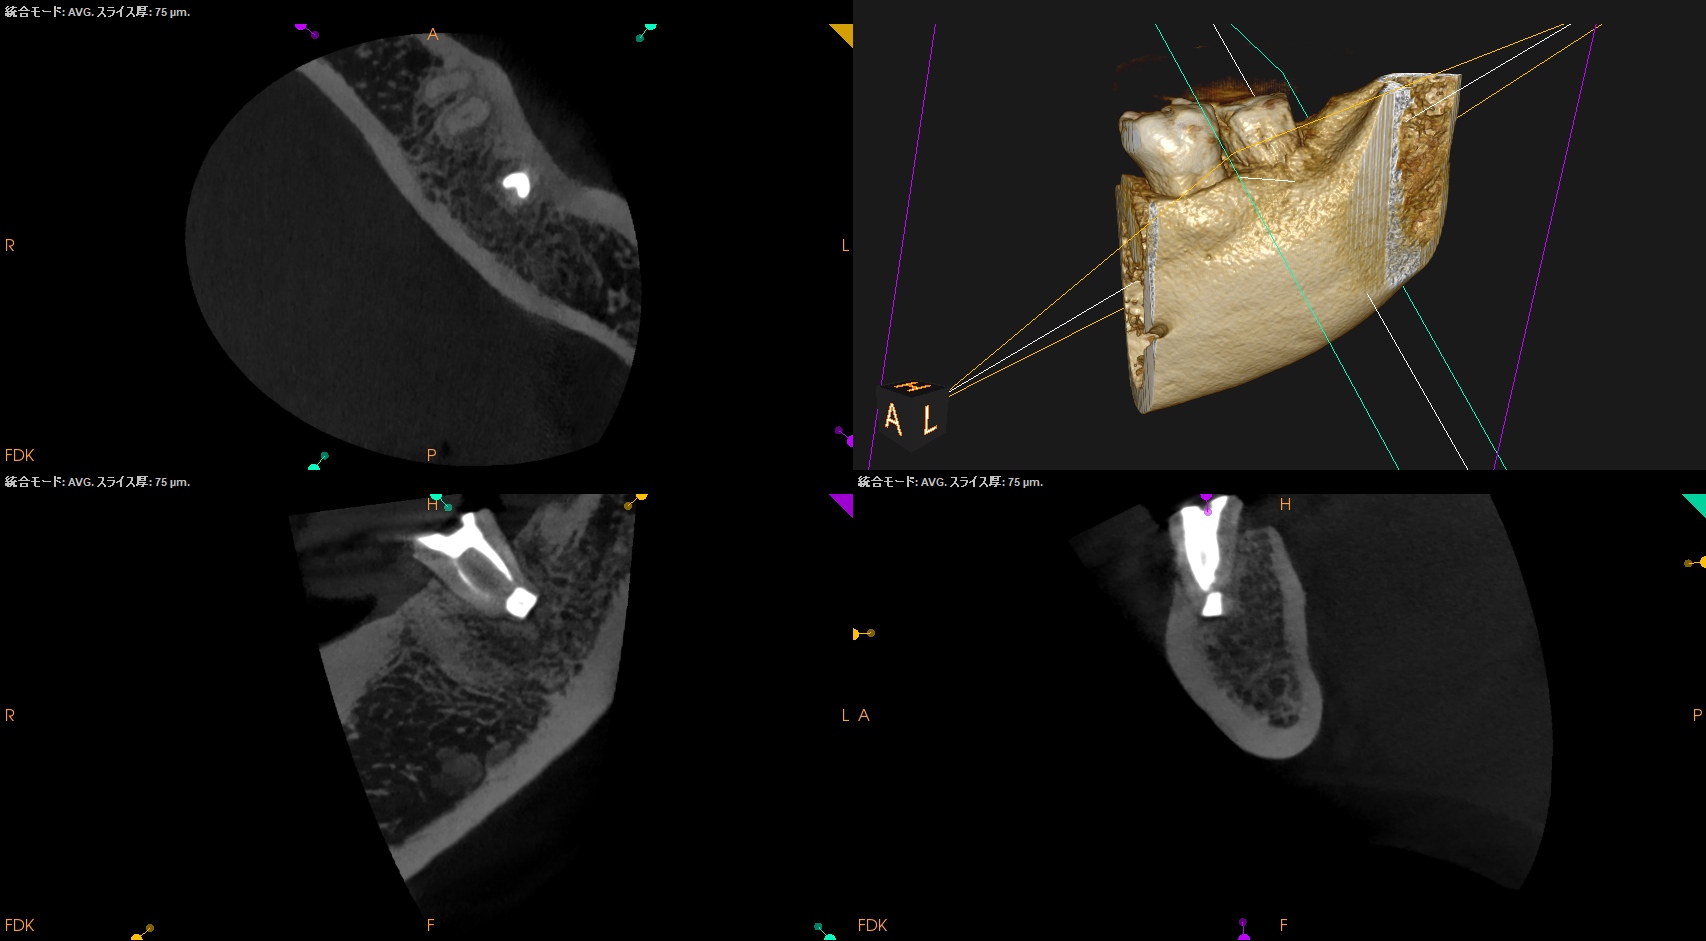

紹介患者さんの経過観察。

1.5yr前にIntentional Replantationを行っていた。

その経過観察だ。

初診時にあった歯肉の腫脹(↓)は消失していた。

初診時と比較した。

5年前から悩まされていた歯肉の腫脹は消失し、歯槽骨も完治した。

打診検査時のアンキローシス音もないことからこの日で終診とさせていただいた。